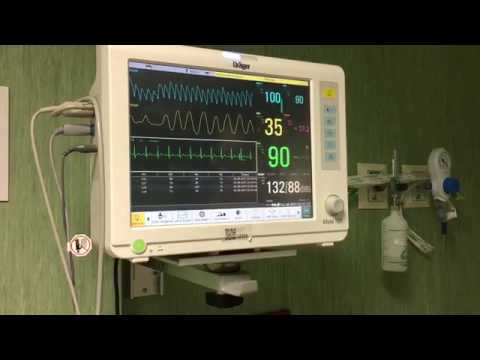

Paciente de 72 años con SCA que presenta TV polimórfica y FV que logra revertirse. Dr. Raimundo Barbosa Barros. Fortaleza, Brasil